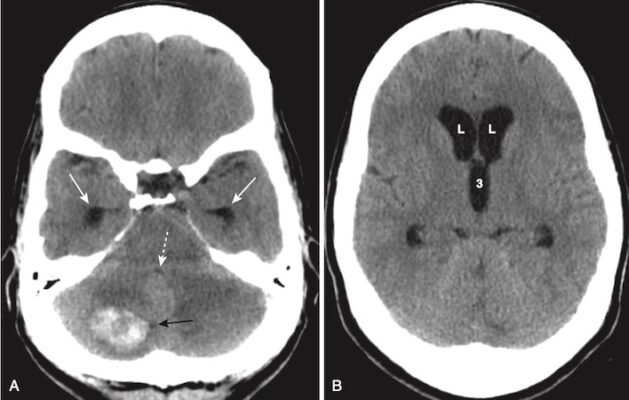

Đột quỵ do xuất huyết (Hemorrhagic Stroke)

- Xuất huyết xảy ra trong khoảng 15% các trường hợp đột quỵ. Xuất huyết có liên quan đến tỷ lệ bệnh tật và tử vong cao hơn đột quỵ thiếu máu cục bộ. Xuất huyết do đột quỵ có thể xảy ra vào nhu mô não hoặc khoang dưới nhện.

- Trong phần lớn các trường hợp, có tăng huyết áp kèm theo. Khoảng 60% trường hợp xuất huyết do tăng huyết áp xảy ra ở hạch nền. Các vùng khác thường liên quan là đồi thị, cầu não và tiểu não (Hình 18).

- Nhận biết xuất huyết trong não (nói chung):

- Máu tươi mới thoát mạch hematocrit bình thường có thể nhìn thấy như là tăng tín hiệu trên phim chụp CT não không cản quang ngay sau biến cố (xem Hình 18). Điều này được cho là do protein trong máu (chủ yếu là hemoglobin).

- Phân tán máu vào hệ thống não thất có thể xảy ra trong chảy máu não do tăng huyết áp (xem Hình 11).

- Khi cục máu đông bắt đầu hình thành, máu trở nên đậm hơn trong khoảng 3 ngày do cục máu đông bị mất nước.

- Sau ngày thứ 3, cục máu đông giảm đậm độ và không nhìn thấy được trong vài tuần tiếp theo. Cục máu đông giảm đậm độ từ bên ngoài vào trong do đó nó có vẻ như co rút lại.

- Sau khoảng 2 tháng, có thể chỉ còn lại một vùng nhỏ giảm đậm độ (Hình 19; Box 1).